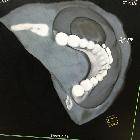

CT

Classic appearances are of a superficial circumscribed, low attenuation mass (typically approximately -65 to -120 HU) with minimal internal soft-tissue component. Again, areas of calcification may be present although are more frequently associated with well-differentiated liposarcoma .

Deeper or larger lesions may have scattered areas of internal soft-tissue density, often more apparent on CT versus MRI. These may represent areas of fat necrosis, fibrous tissue, blood vessels, or muscle fibers; these lesions cannot be confidently differentiated from liposarcoma by imaging.

Intramuscular lipomas may invade and interdigitate with the associated skeletal muscle, resulting in a characteristic striated appearance which may help distinguish from liposarcoma .